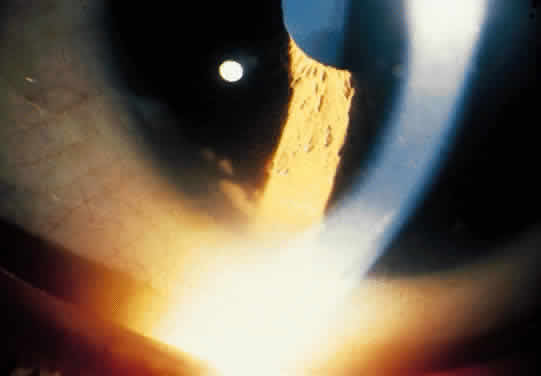

Fuchs' heterochromic iridocyclitis is characterized as a unilateral chronic iridocyclitis of insidious onset. Small, white, round keratic precipitates (Fig. 3) usually are scattered uniformly over the superior and inferior cornea, with fibrin stellate-shaped flecks on the endothelium. Cells and flare are present in the anterior chamber, but are sometimes minimal. Thinning of the iris stroma (Figs. 4 and 5) leads to the change in iris color. Iris transillumination is sometimes visible in the affected iris owing to loss of stroma and pigment epithelium of the iris. It is rarely bilateral, so that the ability to recognize the contrast in iris stroma changes, as well as the distribution of the characteristic corneal precipitates, may help to make this diagnosis. Posterior subcapsular cataract changes (Fig. 6) may progress to a maturing cataract (Fig. 7) in the later stages. Because the disease process may be asymptomatic, the cataract changes may produce the initial symptoms of decreased vision. Posterior subcapsular changes are similar to those seen in other chronic iridocyclitis and are probably due to the metabolic effects on the lens from changes in the aqueous. Vitreous cells and coarse opacities are usually present, and no posterior pole abnormalities are usually observed.27–30 Reports of heterochromic iridocyclitis associated with inactive Toxoplasma retinochoroiditis and sarcoidosis suggest a correlation may exist, at least in some clinical situations.31–35 This indicates that there may be a common ultimate clinical response in the eye that is related to several causes.

Fig. 6. Posterior subcapsular cataract changes in heterochromic cyclitis.

Fig. 7. Maturing cataract changes in heterochromic cyclitis.